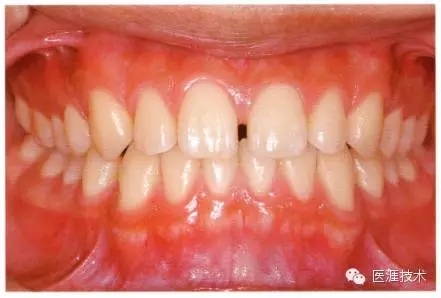

圖為18歲男性,無特殊全身疾病,不抽煙。持續(xù)保養(yǎng)10年。牙菌斑控制比以前好,因刷牙稍稍過度臉頰側(cè)有牙齦萎縮傾向,但牙齒及牙周組織仍保健康。